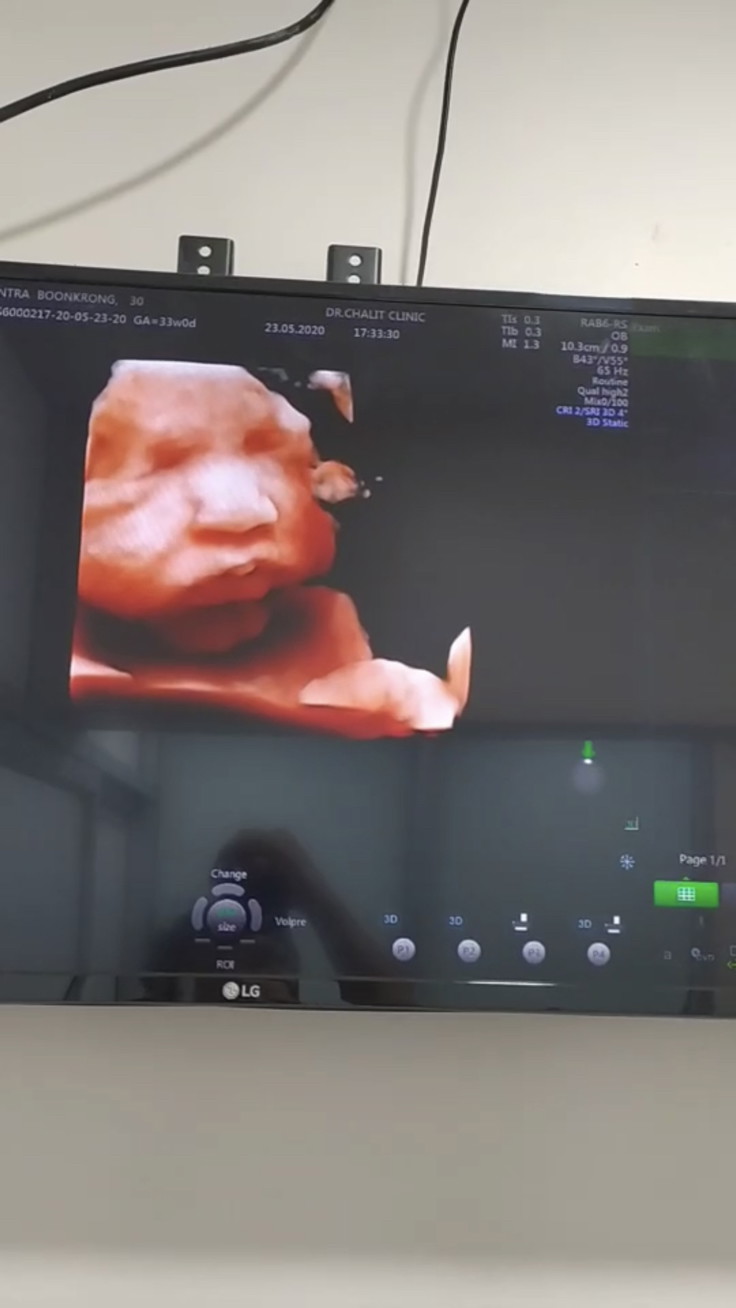

33wจ้า